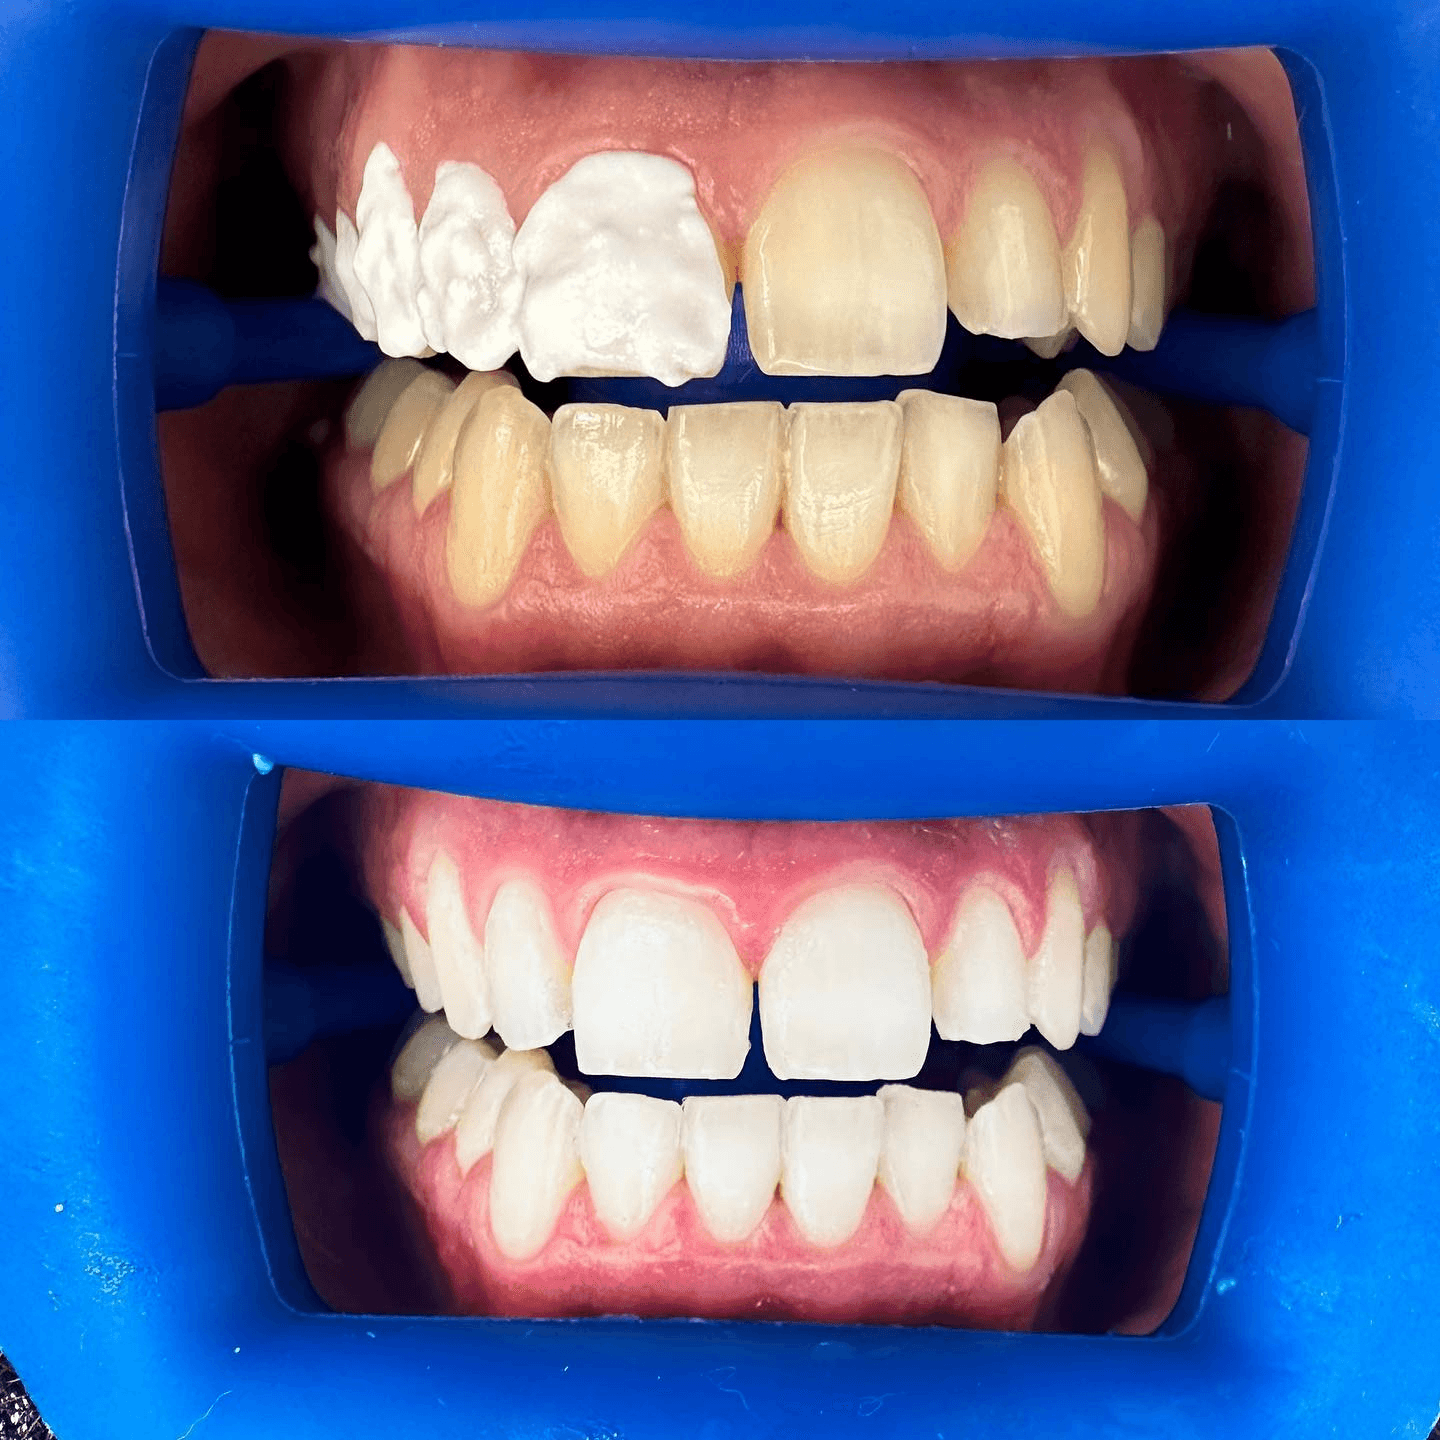

גלריה

צילומים מהמרפאה - מוצגים בהתאם להסכמות מטופלים ולכללי הפרסום.

חשוב: יש להציג תמונות לפני/אחרי רק בהסכמת מטופלים ובהתאם לכללי הפרסום הרפואי.